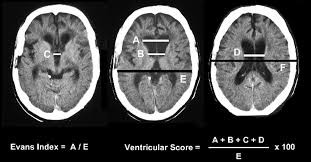

¿Qué prueba considera de mayor utilidad para el seguimiento de la dilatación ventricular?: